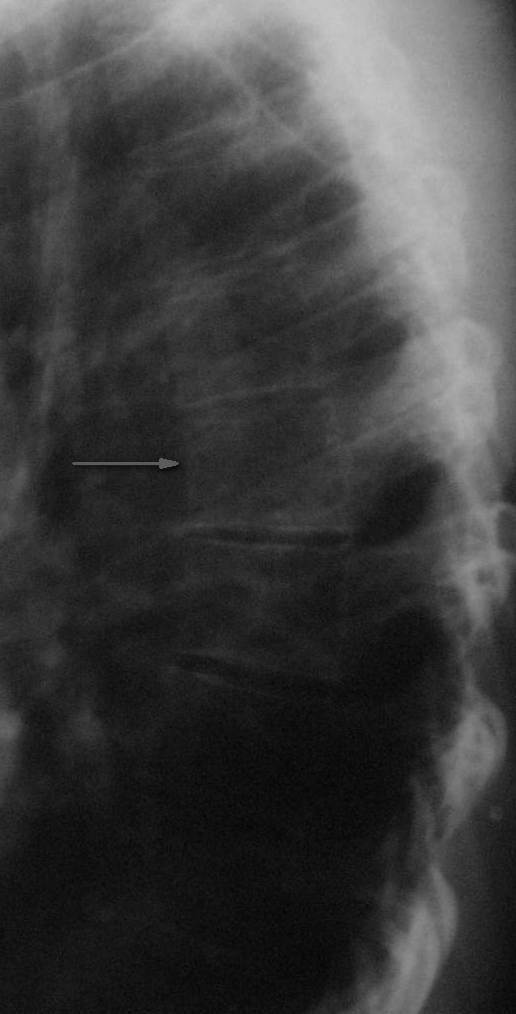

Re: Компрессионный перелом?

Конечно же можно. Седьмой грудной позвонок указан стрелкой.